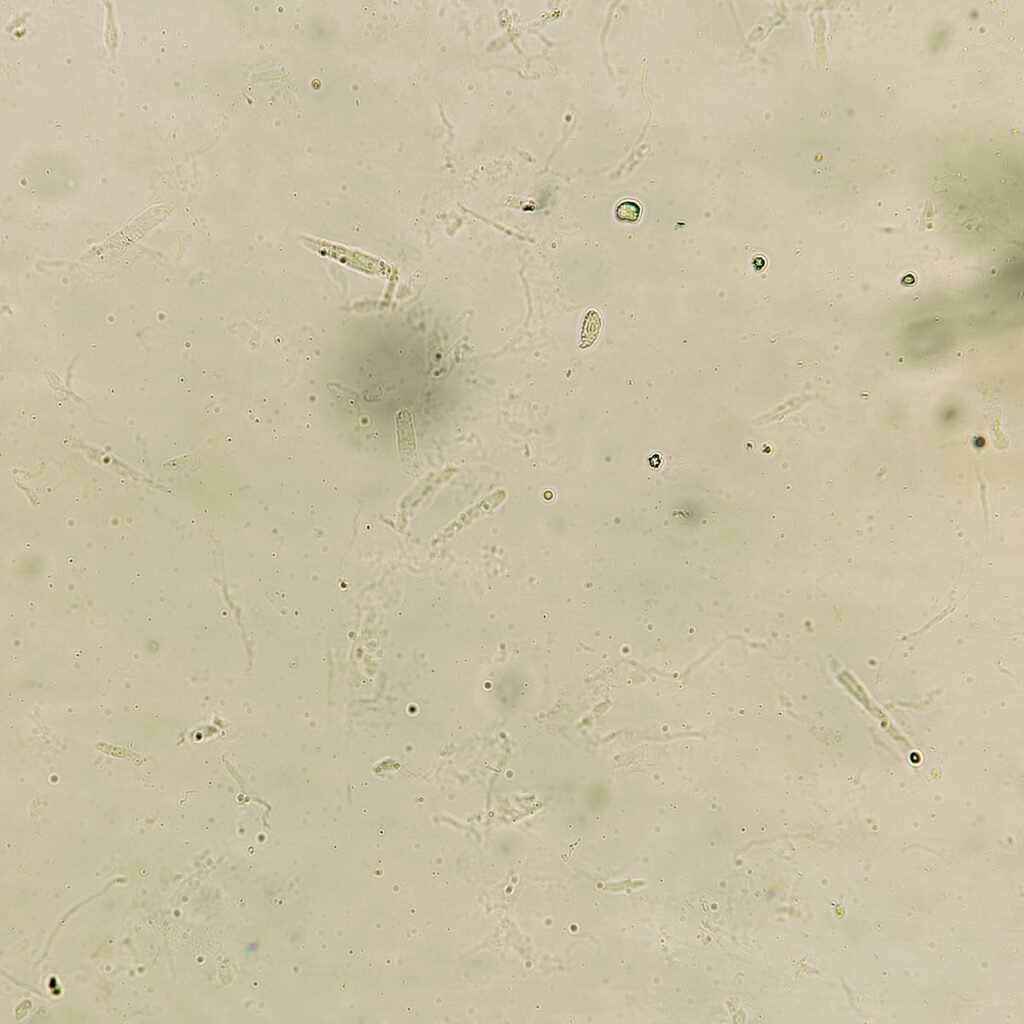

Low Power Field

Scan through on low power to check for & quantitate casts.

High Power Field

Everything other than casts are quantitated on high power.

Hyaline casts are the most notable element in this urine with about 20-30 per low power field seen. Due to the low refractive index of hyaline casts, phase microscopy can greatly aid in quantitation. Between 0-2 red blood cells and white blood cells can be seen on high power field which coincides with the positive blood and leukocyte esterase on the chemistries, respectively. 2+ bacteria is also noted.